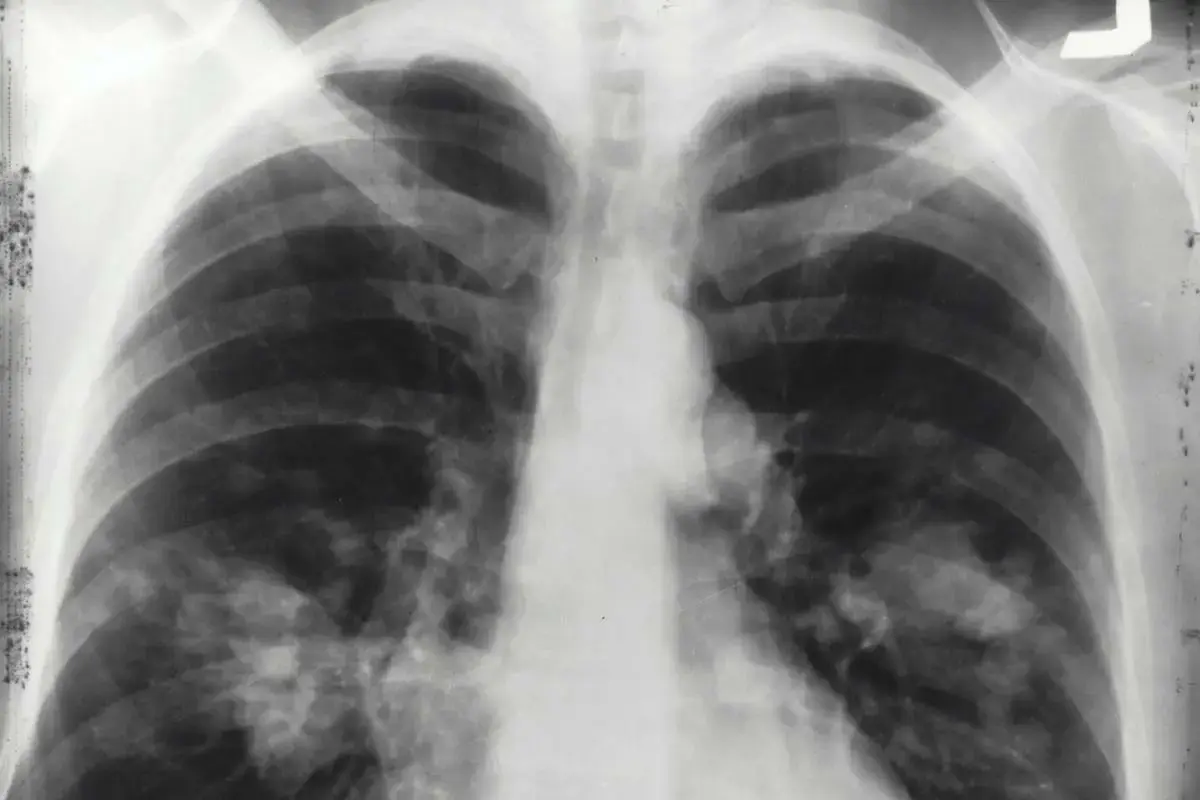

La riabilitazione respiratoria si rivolge a pazienti affetti da BPCO (Broncopneumopatia Cronica Ostruttiva), enfisema polmonare o altre patologie croniche dell’apparato respiratorio. Seguo i protocolli nazionali e internazionali più aggiornati per migliorare la funzione respiratoria, ridurre la dispnea e prevenire complicanze post-operatorie.

I programmi includono esercizi respiratori, tecniche di drenaggio, educazione al controllo del respiro e training fisico personalizzato.Offro inoltre percorsi riabilitativi specifici per pazienti cardiochirurgici o con insufficienza respiratoria post-resezione polmonare, sia in sede ambulatoriale sia a domicilio.